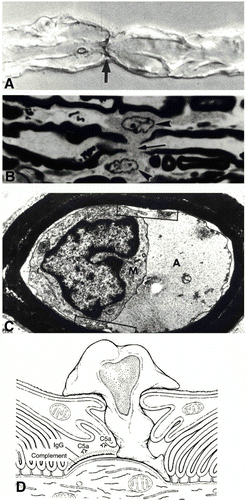

Figure 3. Immunopathology of AIDP. A) Immunostaining showing C3d surrounding two nerve fibers indicated by asterisks (*) B) Complement activation and influx of calcium along with demyelination. C) Complement-mediated activation of macrophages. D) Depiction of pathology in AIDP involving complement activation and macrophage-mediated demyelination. (Image from Ho et al., 1998. Copyright 1998 by Annual Reviews, Inc. Permission pending. )

Cytomegalovirus (CMV), a cause of respiratory tract infections, is the second most common pathogen linked to cases of GBS in Europe and Japan. Autoantibodies against the human ganglioside GM2 have been isolated in patients with a CMV infection and GBS symptoms. However, no definitive epitope mimics have been described despite the fact that CMV is correlated with so many cases of AIDP. Development of AIDP is seen predominantly in the cranial and sensory nerves as opposed to motor nerves. Also, the immune response elicited in AIDP is focused on the schwann cell or myelin sheath. Damage to the myelin or schwann cell results in demyelination that is characteristic of AIDP (Figure 3) (Kuwabara, 2004).